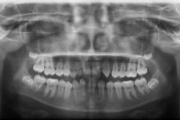

Kaasasündinud hammaste puudumine

Sagedamini puuduvad hambad: teised premolaarid, ülemised lateraalsed intsisiivid, alumised tsentraalsed intsisiivid.